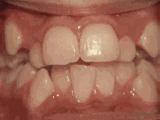

Incisivos laterales faltantes

Este paciente nació sin los incisivos laterales. Usó frenos por 20 meses para corregir la posición de los dientes. Posteriormente, los dientes faltantes fueron reemplazados con puentes fijos “Maryland”.